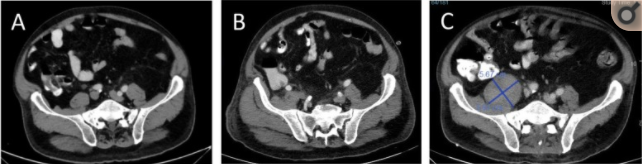

术后第8天,血培养结果回报克雷伯杆菌及肠球菌感染,将抗生素升级为亚胺培南,但患者仍有腹痛症状,无腹膜炎体征,C-反应蛋白160mg/L,白细胞计数13x109,中性粒细胞比例83%,再次复查全腹CT,发现肝脏VII段低密度灶增大,考虑化脓性肝脓肿,如图1b,但此次增强CT发现患者右侧腰大肌脓肿,如图2a,决定继续抗炎及对症治疗,未行引流,两天后,患者腹痛减轻,肝功能基本恢复正常。患者出现腰痛及行走困难,查体发现L4-L5棘突压痛,行腰椎磁共振(MRI),出现了脊髓神经根压迫,并在ERCP术后第19天出现了骨脓肿,转至骨科行手术治疗,术中行L5椎间盘局部切除,骨膜外脓肿切开引流,留置引流管。术后脓液培养为克雷伯杆菌阳性,继续抗炎治疗,但患者仍有发热症状,术后第7天出现肝脓肿,病灶为肝VII段低密度不规则病变,大小约4.8cm,如图1C。后续患者继续抗炎治疗6周,引流通畅,切口预后良好,复查腹部CT,脊髓MRI,肝脓肿和骨脓肿消失,出院6周后再次行腹腔镜胆囊切除术。

图2 ERCP术后复查腹部CT,发现腰大肌脓肿,3天(a),7天(b),26天(c)